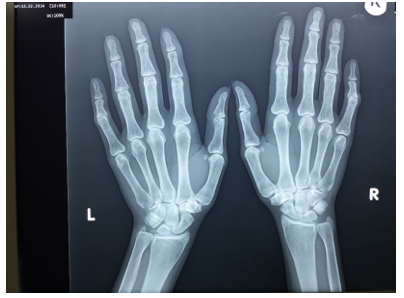

Figure 7 Frontal X-ray of both hands shows bilateral subperiosteal resorption of the radial sides of middle phalanges of middle fingers (pathognomonic of secondary hyperparathyroidism).